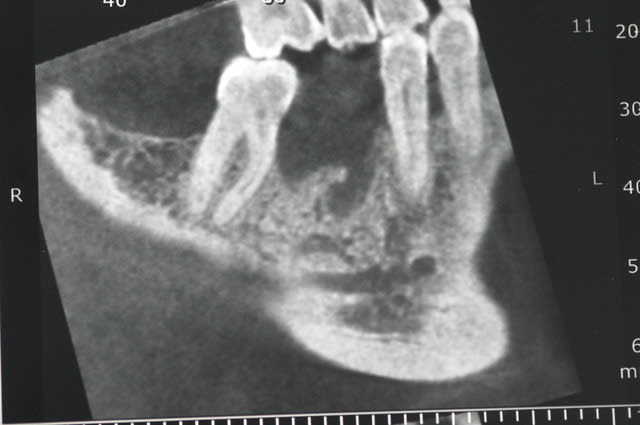

ci joint les photos des coupes scanner d'un patient à qui j'ai proposé de poser un implant afin de remplacer la 36. sur les coupes, on vois nettement le dédoublement du NAI.

Après discussion avec le radiologue qui ni avait pas fait allusion dans son compte rendu, celui-ci me dit que le canal le canal ne contient que quelques filet nerveux (je ne sais pas comment il peut voir cela..) et que je peux passer au travers sans problèmes.

tient pour revenir sur ce que disait Pxav, sur une image comme celle ci, vous passeriez en vestibulaire? c'est vrai qu'il y a de la place, mais je n'ai pas osé...